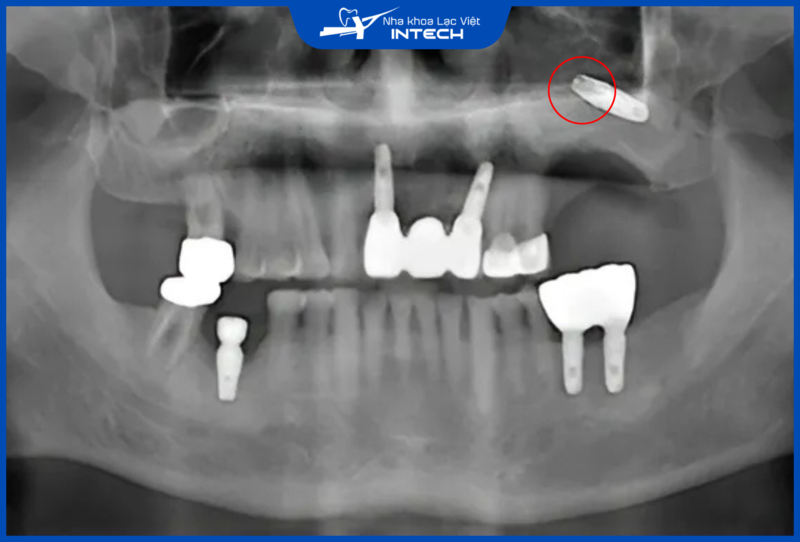

Trồng răng Implant là một thủ thuật đòi hỏi bác sĩ phải có chuyên môn cao và sử dụng công nghệ hiện đại để xác định chính xác vị trí đặt trụ. Nếu quá trình này được thực hiện bởi bác sĩ thiếu kinh nghiệm hoặc không áp dụng kỹ thuật đúng, có thể xảy ra va chạm vào các mô mềm, dây thần kinh và các vùng lân cận.

Bác sĩ thiếu kinh nghiệm có thể cắm Implant quá sâu, gây đứt ống thần kinh hàm dưới

Sai sót này không chỉ gây đau đớn và chảy máu kéo dài, mà trong một số trường hợp nghiêm trọng, có thể dẫn đến tê liệt môi, má hoặc các khu vực khác trên khuôn mặt. Hậu quả của việc tổn thương dây thần kinh có thể để lại di chứng lâu dài, ảnh hưởng đến chức năng sống và thẩm mỹ khuôn mặt của cô chú/anh chị.

Để tránh những biến chứng nguy hiểm này, cô chú/anh chị bắt buộc phải lựa chọn kỹ bác sĩ có tay nghề cao và am hiểu sử dụng công nghệ tiên tiến.

Bác sĩ tay nghề kém có thể xảy ra tình trạng cắm Implant âm phạm xoang hàm trên, gây ra các biến chứng như viêm xoang, đào thải trụ